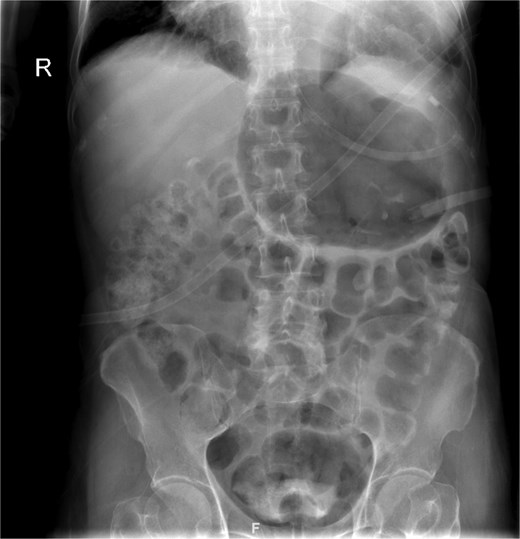

On presentation, the patient was fully oriented with vitals in the normal range. On examination, the abdomen was soft and not distended. There was a scar at the lower midline laparotomy for an unknown indication. There was no abdominal tenderness or any signs of peritonitis. All hernial orifices were intact. His laboratory results were unremarkable with a normal renal and electrolytes profile and no leukocytosis or anemia. Abdominal radiograph demonstrates multiple dilated loops of small bowel with prominent air-fluid levels. No evidence of free intraperitoneal air is identified to suggest perforation. No radiopaque foreign bodies or mass lesions are visible (Fig. 1). The patient underwent computed tomography (CT) of abdomen with IV contrast. The stomach demonstrates abnormal orientation with inferior displacement of the fundus and superior displacement of the gastric pylorus near the gastroesophageal junction, with gastric distension. Mild perigastric and perisplenic fluid. Preserved gastric wall enhancement. Mild pelvic fluid is noted (Fig. 2).

Abdominal radiograph in an anteroposterior (AP) projection demonstrates multiple dilated loops of small bowel with prominent air-fluid levels. The large bowel appears decompressed. A nasogastric tube is seen in situ, terminating in the stomach. No evidence of free intraperitoneal air is identified to suggest perforation. No radiopaque foreign bodies or mass lesions are visible.